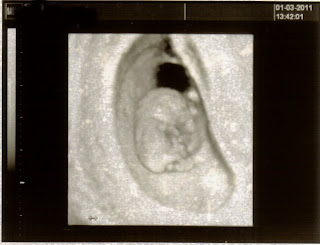

I had my 10 week u/s today and everything looks great! In the picture above my baby is all curled up nice and cozy in it's home for the next 30 weeks. My baby is measuring right on schedule he/she is 1 1/4 inches long and had arms and legs. It kept rubbing it's face in the u/s sooooo adorable. The heartbeat was 175 which we were told is perfect : ) I lost all the bad symptoms of pregnancy this week, so I was a little worried but come to find out everything is just fine. I don't have another u/s for another 3.5 weeks seems like forever away, so until then I will focus on keeping myself and my baby healthy and happy!